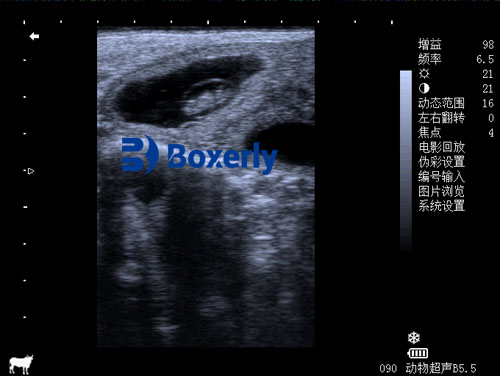

Portable ultrasound machines operate on the same basic principles as human medical devices. They use high-frequency sound waves—typically between 2.5 and 7.5 MHz—that are emitted by a probe (also called a transducer). These sound waves penetrate the animal’s body and bounce back upon encountering tissues of different densities, such as muscles, organs, or developing fetuses.

The returning echoes are translated into visual images on a screen. In portable units, these screens are often built into the probe handle itself, attached to a wearable monitor, or displayed on a linked smartphone or tablet via Wi-Fi or Bluetooth.

Image Quality and Resolution Thanks to high-definition displays and digital signal processing, portable ultrasounds now deliver image clarity comparable to full-size machines. Some units offer adjustable frequency ranges and image optimization presets tailored for specific species or scanning goals.